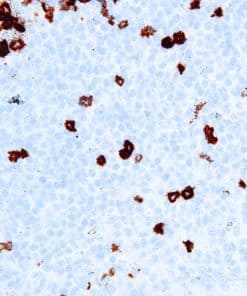

Thymidylate Synthase

Thymidylate Synthase (TS) is a crucial enzyme responsible for the synthesis of 2′-deoxythymidine-5′-monophosphate (dTMP) a precursor for thymidylate which is necessary for DNA replication and repair from 2′-deoxyuridine-5′-monophosphate (dUMP). In terms of cancer, TS is an important target for cancer treatment as the inhibition of TS and therefore nucleotide synthesis necessary for cell growth has shown to be a vital part for successful treatment against colorectal, pancreatic and breast cancers.

| Clone | IHC697 |

| Source | Mouse Monoclonal |

| Positive Control | Colon Cancer |

| Dilution Range | 1:100 – 1:400 |